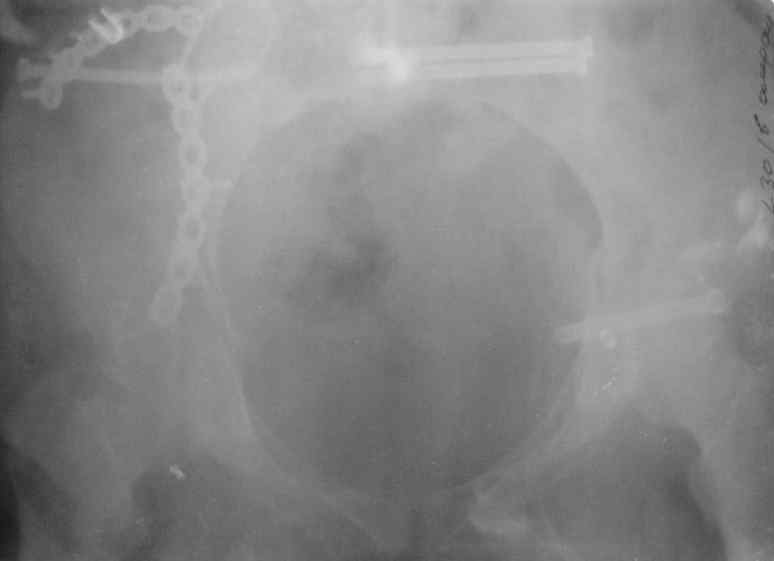

Здравствуйте, коллеги. Какие будут мнения по поводу лечения представляемой больной?

Молодая девушка 19 лет, травма 1 год назад, тогда же прооперирована.

В настоящее время имеются ноющие боли в области крестца слева, нарушение походки, ощущение неуверенности, слабости в левой нижней конечности, неврологически -непостоянные парестезии в левой нижней конечности. Ходит с дополнительной опорой, страдает от ожирения.

В приложении снимки при поступлении и послеоперационные год назад.

Могу сказать одно: миграция винтов и нестабильность синтеза левого подвздошно-крестцовогоо сочленения очевидна.

Вот цитата из статьи с odoс.ru:"Идеально было бы иметь винты диаметром 7 - 8 мм с довольно широкой резьбой в 50 - 80 мм. Также необходимы более длинные винты и, в общем, наиболее часто используемые размеры - между 90 и 150 мм." Думается, в этой статье вы найдете ответы на все ваши вопросы.